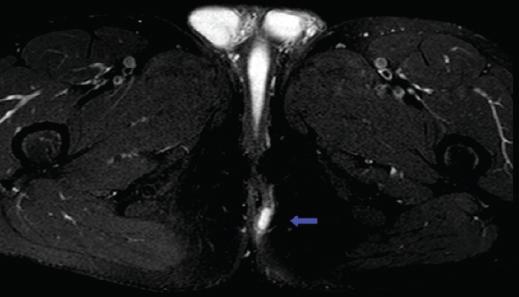

Varón de 39 años, sin cirugías anales previas ni otros antecedentes de interés, valorado en consulta por un cuadro de supuración perianal intermitente de 1 año de evolución. En la exploración física presentaba un orificio fistuloso externo (OFE) localizado a las 2 horas, a 3 cm del margen anal en posición de litotomía, con supuración activa y sin alteraciones en el tacto rectal. Las imágenes ponderadas en T2 de la resonancia magnética (RM) pélvica (Fig. 1), aparentemente, mostraron una fístula transesfinteriana anterior con una pequeña colección hiperintensa en el pliegue interglúteo. Ante la sospecha de fístula anal se realizó una exploración quirúrgica (Fig. 2), observando un OFE localizado a las 2 horas, con signos de abscesificación, y otro OFE a las 7 horas en litotomía. Así mismo, asociaba un orificio pilonidal en la región coccígea. Se canularon los OFE y se inyectó peróxido de hidrógeno, sin evidenciar comunicación con el canal anal en la anuscopia, al contrario de lo que sugería la RM. El OFE a las 2 horas comunicaba con la cavidad abscesual y el OFE de las 7 horas comunicaba con la fosita pilonidal posterior. Se realizaron fistulotomías, que mostraron cavidades pilonidales crónicas, con gran contenido piloso y de granulación (Fig. 3). Se efectuaron escisiones completas de las cavidades pilonidales y posterior marsupialización de los bordes para favorecer el cierre por segunda intención. Al mes y medio de la intervención (Fig. 4), el paciente se encontraba asintomático, con una correcta cicatrización de las heridas quirúrgicas. Tras 2 años de seguimiento, el paciente no muestra datos de recidiva.

Figura 1 Resonancia magnética pélvica (imagen ponderada en T2) que muestra una fístula transesfinteriana anterior con una pequeña colección hiperintensa en el pliegue interglúteo (flecha).